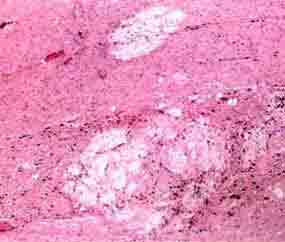

脂肪壞死(fat necrosis)也屬於液化性壞死,分為酶解性和外傷性兩種。前者常見於急性胰腺炎時。外傷性脂肪壞死則大多見於乳房,此時受損傷的脂肪細胞破裂,脂滴外逸,並常在乳房內形成腫塊,光鏡下可見其中含有大量吞噬脂滴的巨噬細胞(泡沫細胞)和多核異物巨細胞。

液化性壞死(liquefactive necrosis):是壞死組織因酶性分解而變為液態。最常發生於含可凝固的蛋白少和脂質多的腦和脊髓,又稱為軟化(malacia)。